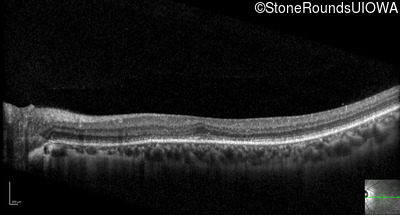

Optical Coherence Tomography - Right - 20/25 -3

Exemplar / OCT Stack